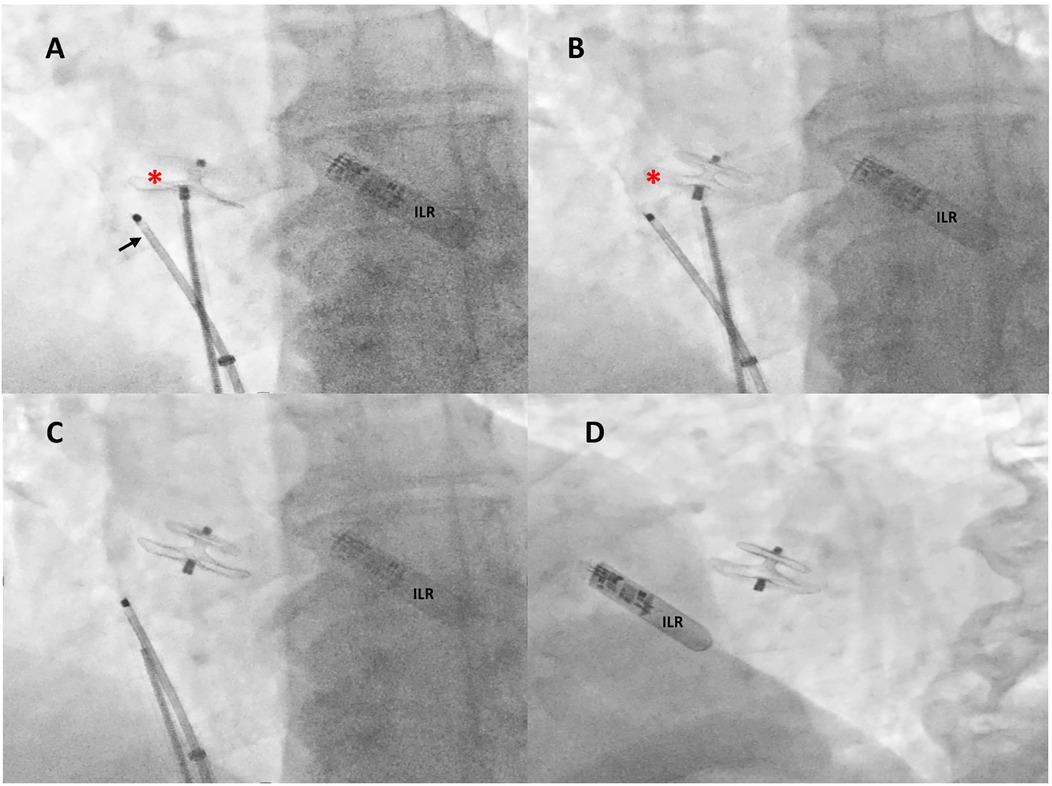

X-ray images in four panels (A, B, C, D) show cardiac procedures. Panel A highlights a catheter with an arrow and a red asterisk, near an Implantable Loop Recorder (ILR). Panel B repeats this view without the arrow. Panels C and D show the ILR and a cardiac device without annotations.

Figure 3. Intraprocedural fluoroscopic procedural steps. Under rotational intracardiac echocardiography (black arrow) and using a dedicated 9-F-long sheath, a 18/24 mm MemoPart PFO occluder (red asterisk) connected by a microscrew to a delivery cable was positioned across the PFO tunnel (A), the device was then disconnected by turning the delivery cable counterclockwise (unscrewing) (B), and the final correct position of the device was confirmed by fluoroscopy in anteroposterior (C) and left anterior oblique 30° view (D). ILR, loop recorder.

A Doppler study of the lower limbs revealed no overt thrombosis. Ultrasound examination of extracranial blood-supplying arteries was normal, and carotid dissection was excluded. Thrombophilic disorders were ruled out. c-TCD showed a large RLS with >20 bubbles with a shower pattern in basal conditions, so Valsalva strain was not performed. Neurological symptoms progressively improved. Following heart–brain team discussion, transcatheter PFO closure was recommended, and the patient was transferred to our institution on 22 December 2024. After written informed consent, he underwent percutaneous PFO closure under local anesthesia and mild sedation, with fluoroscopic and rotational intracardiac echocardiography (rICE) guidance using a 9 F–9 MHz Ultra ICE catheter-based ultrasound probe (Boston Scientific Corporation, USA) (Figure 2) as previously described (10). Heparin (5,000 UI i.v.) was administered. A 9-F-long sheath was used to deliver an 18/24 mm MemoPart PFO occluder (Lepu Medical Technology, Beijing Co., Ltd.) connected by a microscrew to a delivery cable. From a femoral venous approach, the guiding sheath was passed through the PFO. Under fluoroscopic and rICE guidance, the device was advanced, and the small distal disk was released in the left atrium (LA) and pulled against the septum. The bigger right atrial disk was then deployed in the right atrium (RA) by pulling back the sheath, and finally the device was disconnected by turning the delivery cable counterclockwise (unscrewing) (Figure 3). Following device implantation, rICE demonstrated correct device placement with no residual shunt after injection of agitated saline solution (Figure 4). Moreover, ASA was completely stabilized and sandwiched between the two disks of the device. The patient was discharged home in good clinical condition on dual antiplatelet therapy with aspirin 100 mg/day and clopidogrel 75 mg/day for 6 months; endocarditis prophylaxis was also recommended. Persistent clinical improvement and no residual shunt at 2D TTE color Doppler were confirmed at 7-month follow-up.